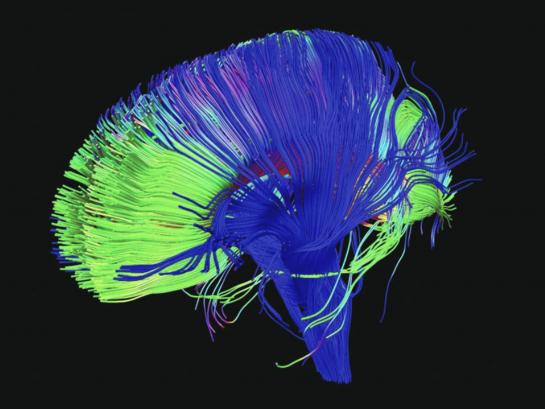

Тело человека / The Human Body (1) История жизни (1998) Кристофер Спенсер (док. сериал, BBC) by Роман Вольтов Videos 49:08 49:16 49:23 49:07 49:33 49:04 49:31 49:06